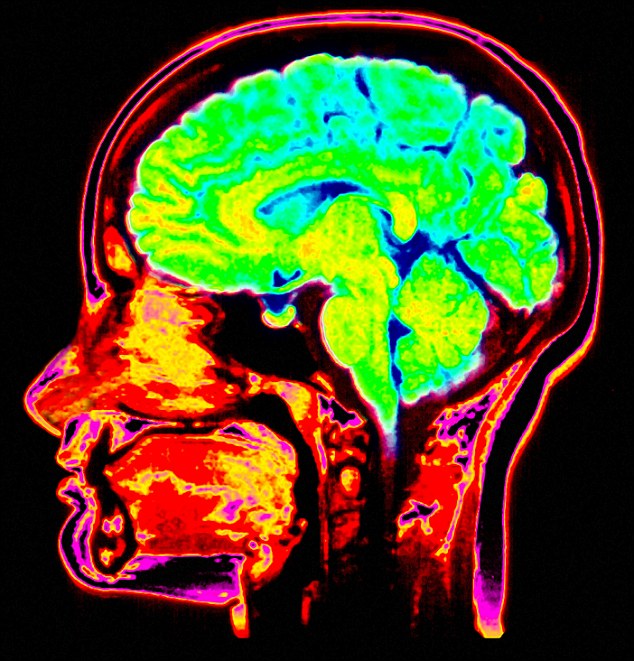

The scientists monitored the dreamers with both magnetic resonance imaging and near-infrared spectroscopy to see patterns of heat in their subject’s heads, which gives a picture of brain activity.

The scientists used a combination of magnetic resonance imaging and near-infrared spectroscopy to 'see' hot and cold patches in their brains. The activity was identical when people did something consciously, and did it in a dream.